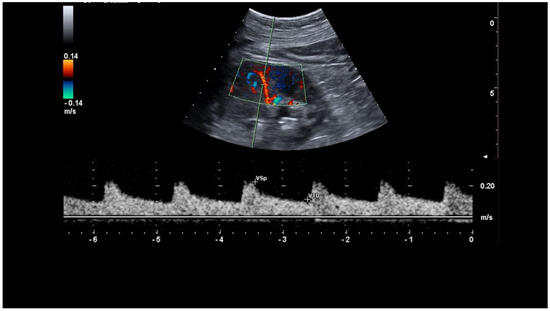

- Samoni, S.; Nalesso, F.; Meola, M.; Villa, G.; De Cal, M.; De Rosa, S.; Petrucci, I.; Brendolan, A.; Rosner, M.H.; Ronco, C. Intra-Parenchymal Renal Resistive Index Variation (IRRIV) Describes Renal Functional Reserve (RFR): Pilot Study in Healthy Volunteers. Front. Physiol. 2016, 7, 286. [Google Scholar] [CrossRef]

- Samoni, S.; Villa, G.; De Rosa, S.; Husain-Syed, F.; Guglielmetti, G.; Tofani, L.; De Cal, M.; Nalesso, F.; Meola, M.; Ronco, C. Ultrasonographic Intraparenchymal Renal Resistive Index Variation for Assessing Renal Functional Reserve in Patients Scheduled for Cardiac Surgery: A Pilot Study. Blood Purif. 2022, 51, 147–154. [Google Scholar] [CrossRef]

- Tublin, M.E.; Bude, R.O.; Platt, J.F. Review. The resistive index in renal Doppler sonography: Where do we stand? AJR Am. J. Roentgenol. 2003, 180, 885–892. [Google Scholar] [CrossRef]